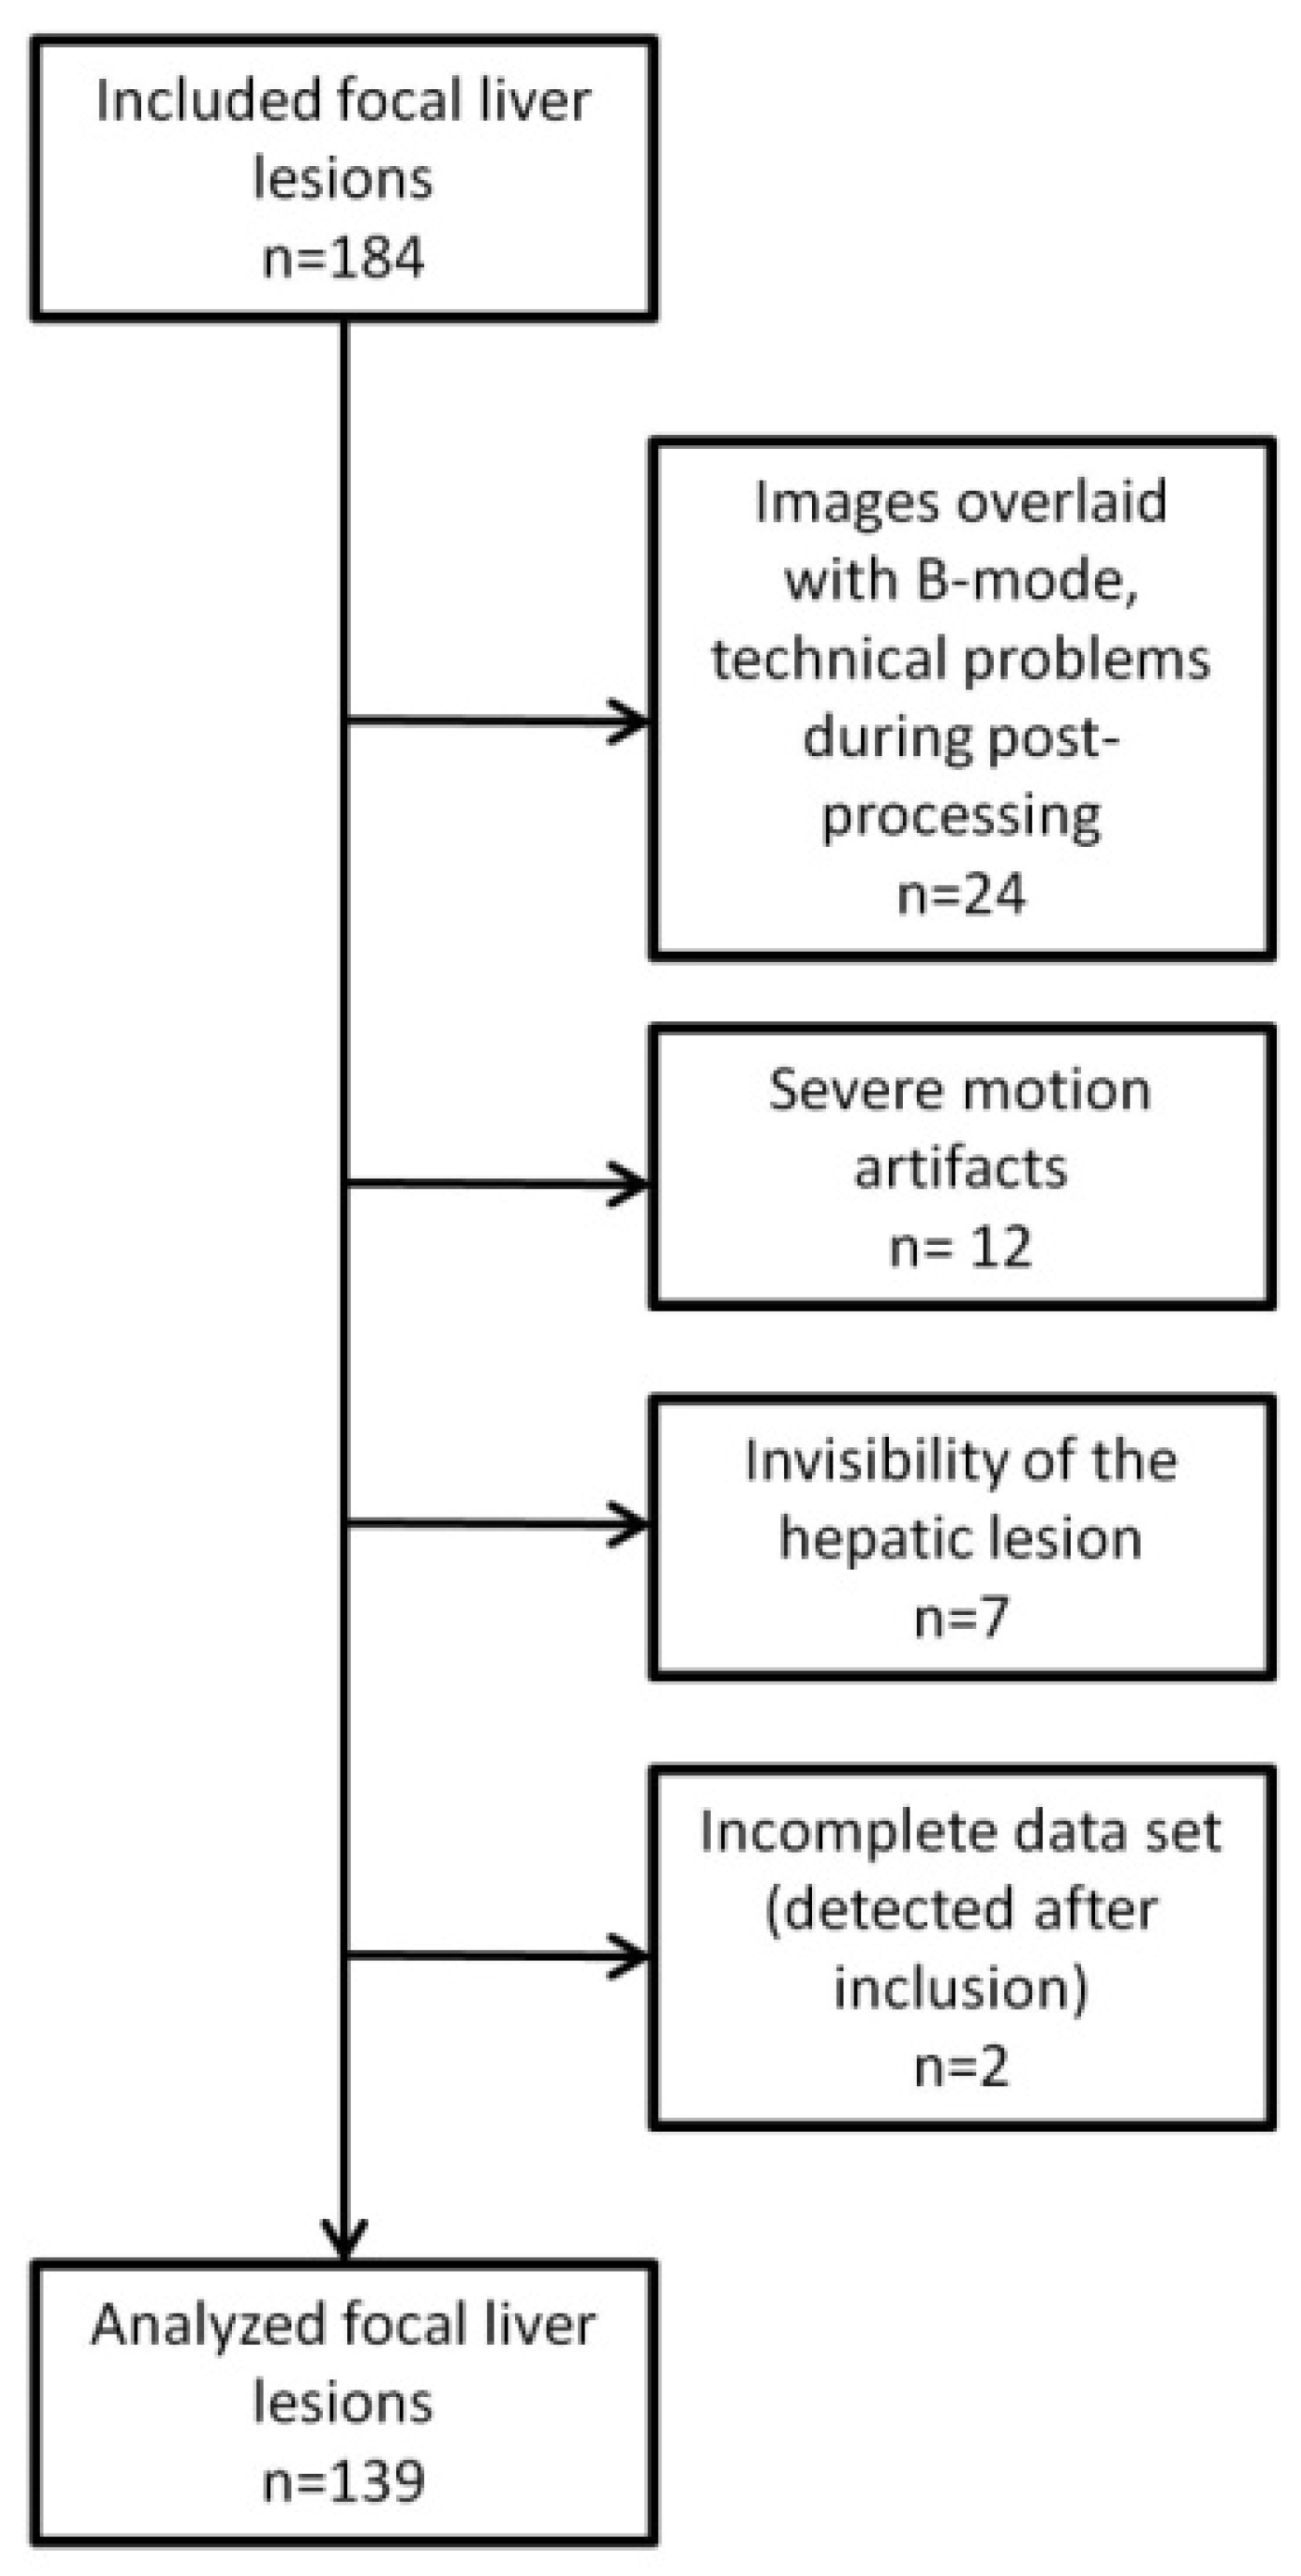

2. Materials and Methods

2.1. Study Cohort